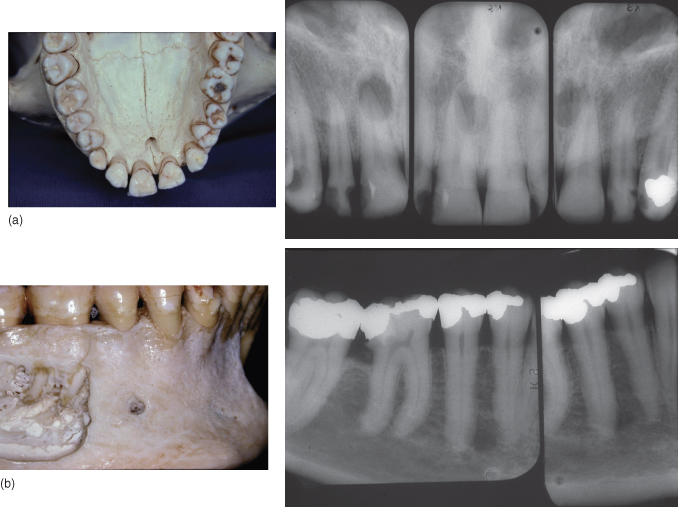

Endodontic treatment 2.2. (a) Periapical Xray endodontic overfilling Endodontic Radiography Techniques Advanced radiographic techniques for endodontic diagnosis. As a review for clinicians, normal and pathologic findings relevant to endodontics are presented. Describe the importance of radiographs in endodontic diagnosis, treatment, and postoperative evaluation. Key radiographic imaging techniques, such as the paralleling and bisecting techniques, as well. Alternative imaging techniques have been. As a review for clinicians, normal and pathologic findings relevant. Endodontic Radiography Techniques.